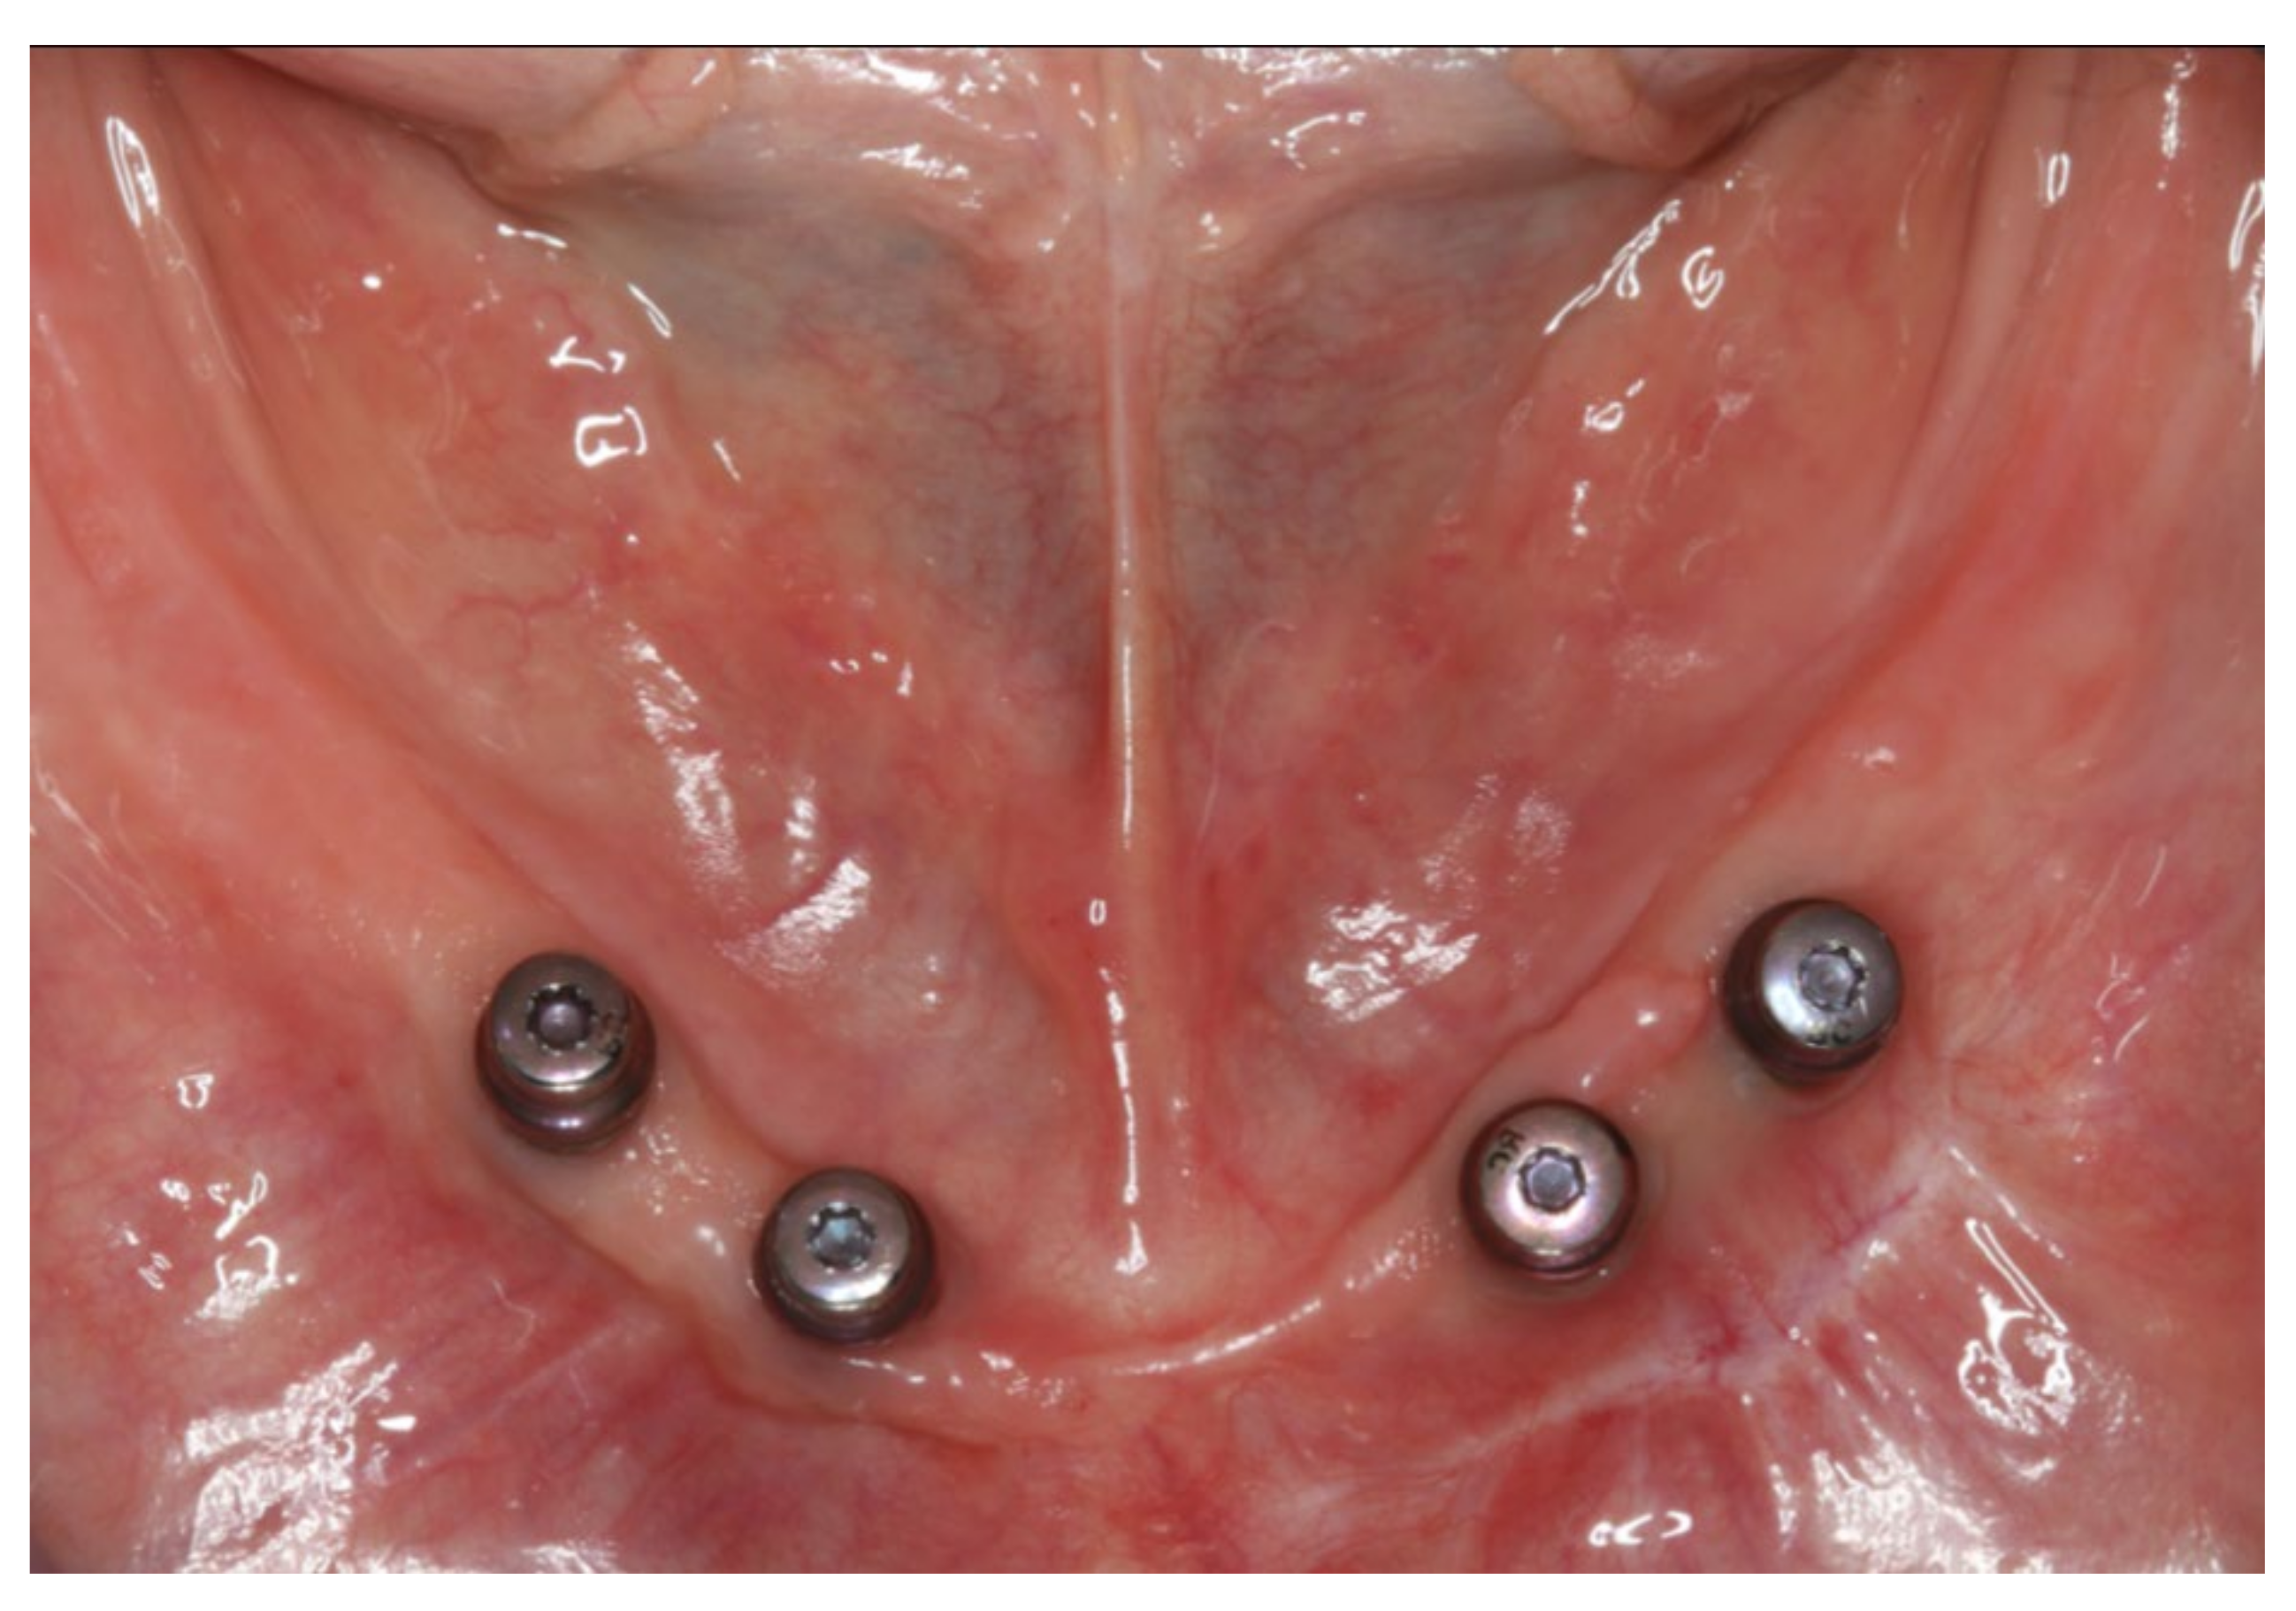

Figure 3.

Intraoral photograph of the lower jaw with four interforaminal implants supplied with healing caps.

Inserted implant-supported overdenture in the lower jaw.

Figure 20.